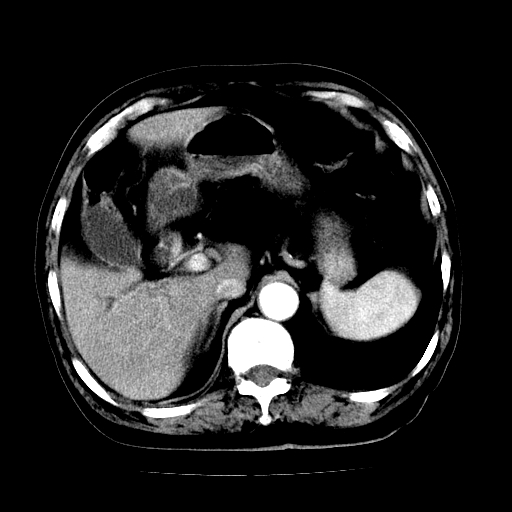

男,71岁,皮肤黄染四天。

考虑中段胆管癌

考虑胆总管癌并肝内外胆管扩张。

胰腺上端胆总管内见软组织影,强化不明显,结合临床,还是考虑低位梗阻性黄疸,胆总管癌可能性大